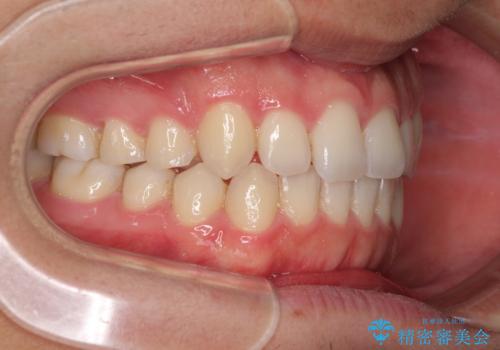

狭い歯列と前歯のデコボコ インビザラインによる矯正治療

- 上下前歯のデコボコを気にして来院された患者様です。

インビザラインによる上下歯列の拡大と、IPR(歯と歯の間を削る)にるスペースの獲得により、前歯のデコボコと狭い歯列を改善することとしました。

比較的軽度な歯列不正であったため、治療期間はそれほど長くはならないと予想されました。

しかしながら、あまりしっかりとマウスピースを装着していなかったため、思いの外期間が長引いてしまいました。

また、仕上がりの歯列にも若干の叢生が残ってしまいました。